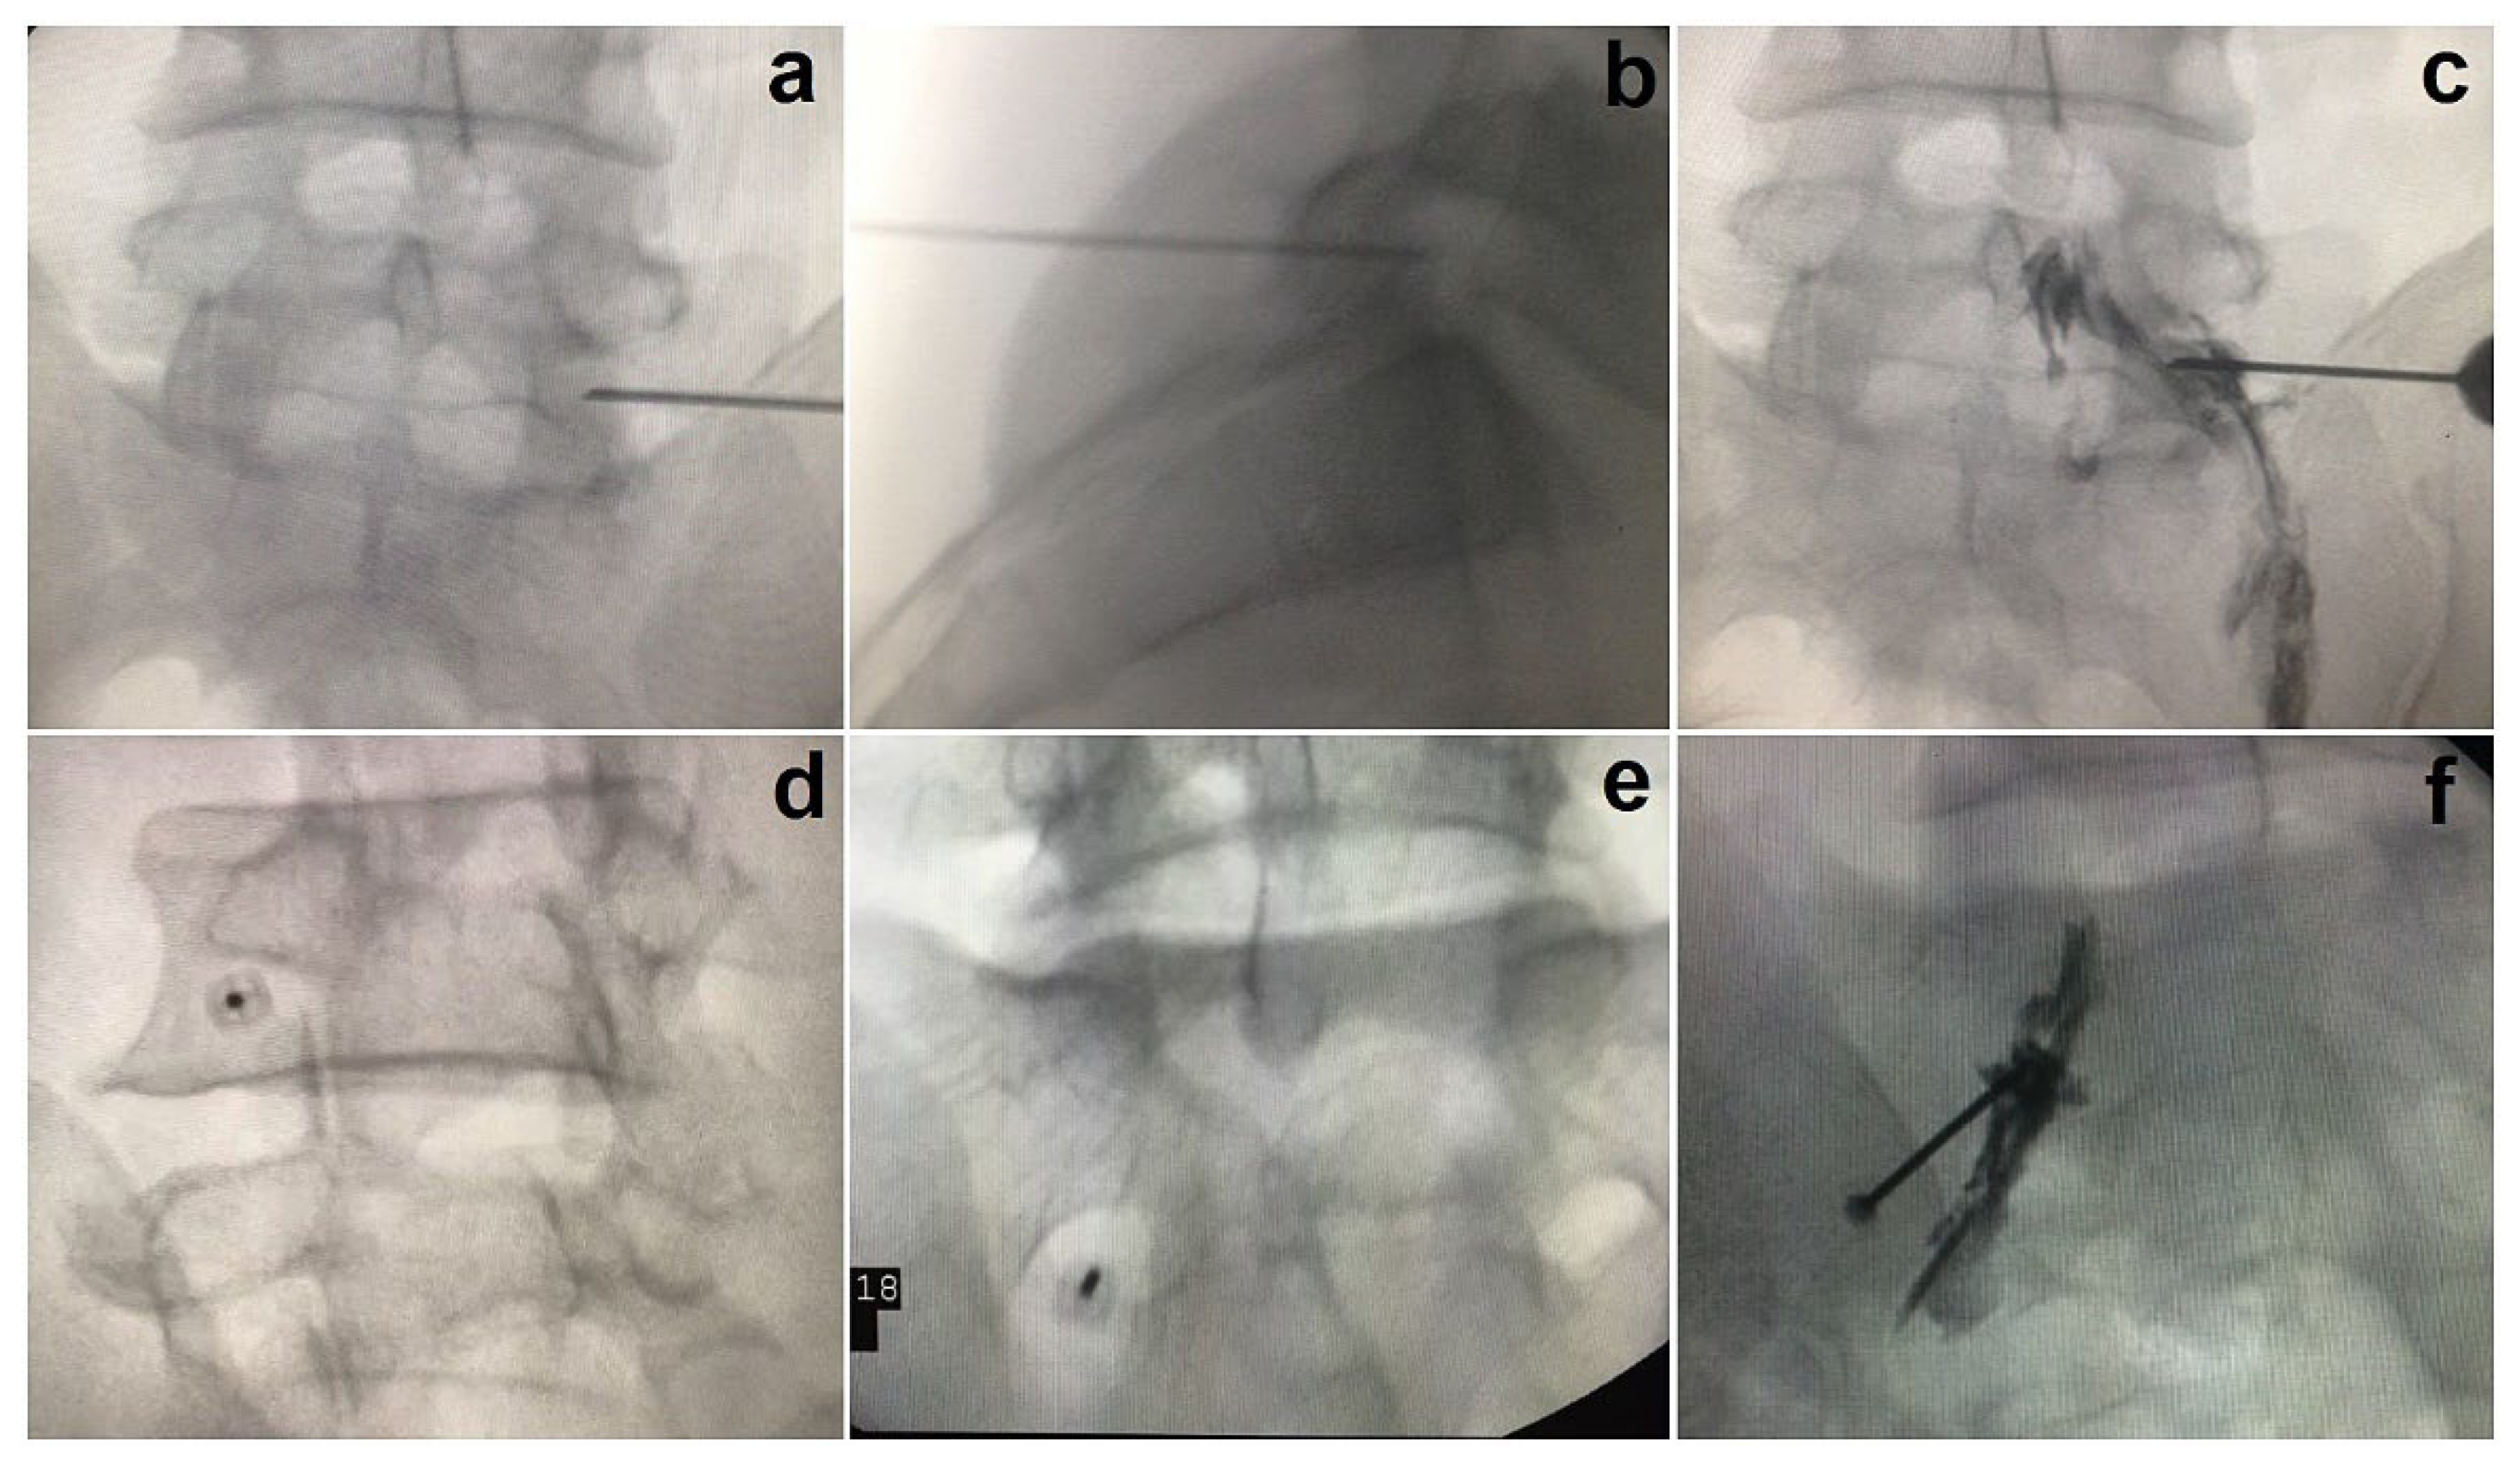

3.2. The Anteroposterior Approach

3.3. The Oblique Scottie Dog Approach

3.4. SNRB Targeting S1

- Kaliya-Perumal, A.K.; Yeh, Y.C.; Luo, C.A.; Joey-Tan, K.Y. Assessment of Anteroposterior Subpedicular Approach and Oblique Scotty Dog Subpedicular Approach for Selective Nerve Root Block. Clin. Orthop. Surg. 2017, 9, 71–76. [Google Scholar] [CrossRef]